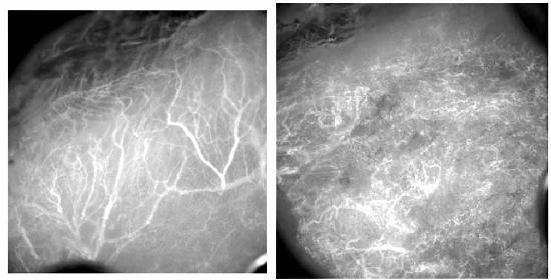

Uma esperança de cura. Uma nova droga, em vez de atacar o câncer diretamente, como faz a quimioterapia, vai à raiz do problema: ela tira o oxigênio e os nutrientes que alimentam o câncer e previne o crescimento de novos vasos sanguíneos no tumor.

“Nossa droga utiliza um receptor chamado CD44, presente na superfície celular, para invadir aquelas células necessárias para o crescimento do vaso sanguíneo do tumor”, afirma a cientista norte-irlandesa, Tracy Robson. “Uma vez lá dentro, o medicamento interfere em uma proteína envolvida na migração das células, prevenindo a angiogênese.”

Como a nova droga funciona alvejando os vasos sanguíneos ainda em formação do tumor, Tracy Robson aposta que ela seja apropriada a uma vasta gama de tumores, inclusive sólidos. Até agora, ela e sua equipe comprovaram boas respostas para os cânceres de mama e de próstata. “O projeto está em desenvolvimento pré-clínico e a primeira fase dos testes clínicos deve começar em 12 meses. Se eles forem bem-sucedidos, o tratamento deverá estar disponível em todo o mundo nos próximos cinco ou 10 anos”, estima a cientista.